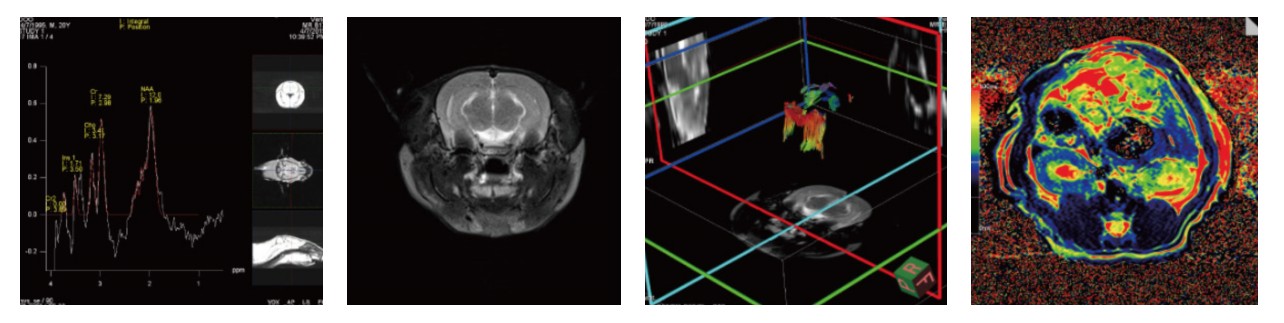

图2 结果展示

四、案例展示

(1)脑部核磁检测应用